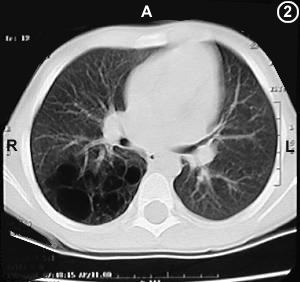

Corte Tomográfico " 2 "

Corte 2 cm por debajo al anterior - (hileo pulmonar):

Muchos quistes en el parenquima pulmonar del lóbulo inferior derecho, note que el resto de la estructura pulmonar es de aspecto normal.

(...mas abajo Corte N° 6 este mismo corte con diferente resolución tomografica para demostrar los quistes.)